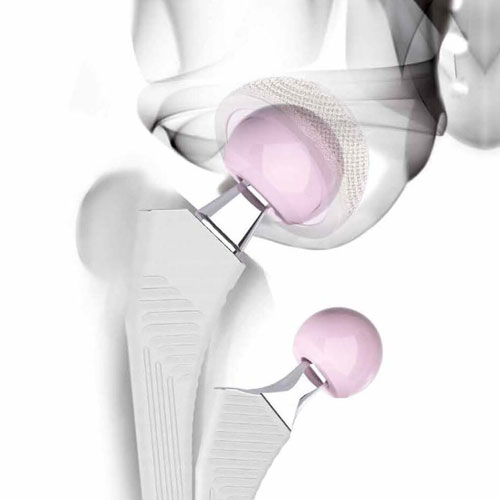

Nato a Roma nel 1953, laureato in Medicina e Chirurgia, specialista in Ortopedia, attualmente Dirige la Struttura Complessa di Ortopedia e Traumatologia presso l’Ospedale Cristo Re, Roma e presso la Casa di Cura Paideia. Si occupa di Ortopedia con particolare riferimento alla chirurgia artroscopia e protesica anche con l’uso del navigatore e di Traumatologia.